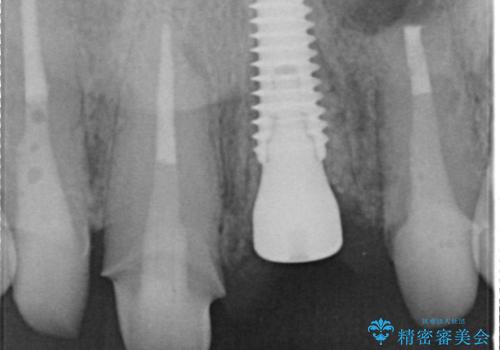

- 治療計画

- 患者様は前歯の審美的な改善を希望されて来院されました。診査の結果、左上1の歯は過去の根管治療により歯根が破折していることが判明し、保存が難しい状態でした。そのため、**長期的な予後を考慮し、抜歯と同時にインプラントを埋入する「抜歯即時インプラント」**を計画。また、隣接する左上2の歯には感染が見られたため、歯根端切除術を同時に行い、感染の除去と治癒を促しました。右上1・2については、セラミッククラウンによる審美修復を行う方針としました。

左上1は抜歯と同時にインプラントを埋入し、骨や歯ぐきの形態を維持しながら治療を進めました。左上2は歯根端切除術により感染部位を除去し、保存治療を実施。右上1・2も含めた前歯4本をセラミッククラウンで修復し、自然な色調と形態を再現しました。治療後は、噛み合わせの安定とともに、美しく自然な前歯を回復することができました。患者様からも「見た目がとても自然で、自信を持って笑えるようになった」と喜びの声をいただきました。